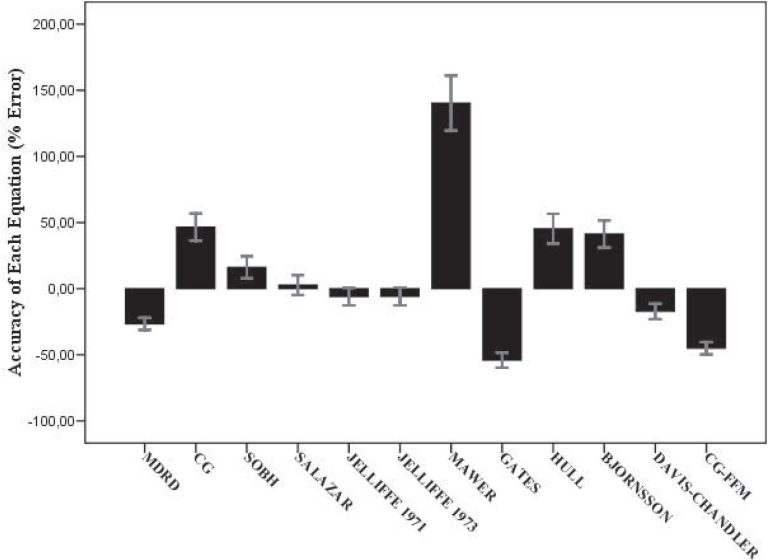

ABSTRACT Objective: Considering that the Cockcroft-Gault formula and the equation of diet modification in renal disease are amply used in clinical practice to estimate the glomerular filtration rate, although they seem to have low accuracy in obese patients, the present study intends to evaluate the predictive performance of 12 equations used to estimate the glomerular filtration rate in obese patients. Methods: This is a cross-sectional retrospective study, conducted between 2007 and 2008 and carried out at a university, of 140 […]

Keywords: Creatinine; Glomerular filtration rate; Kidney; Obesity; Weight loss